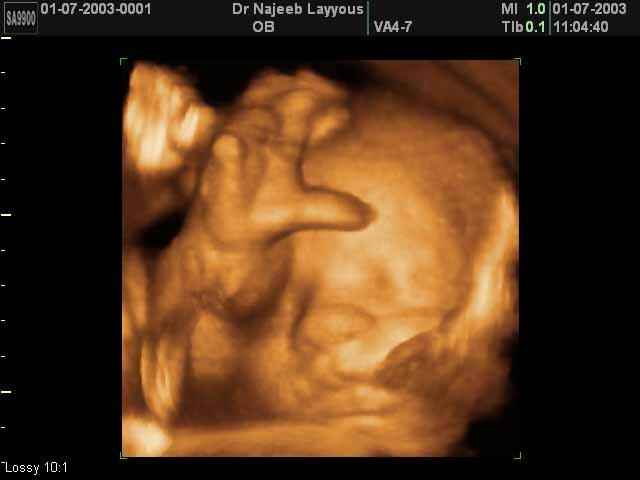

- Fetal Face Ultrasound Photos

- 3D Fetal Profile Ultrasound Scan Photos

- The Clinical Advantages of 3D and 4D Ultrasound

- Definition and Features of Four Dimensional Ultrasound

- Uses of 4D Ultrasound scan

- The importance of 4D ultrasound imaging in pregnancy